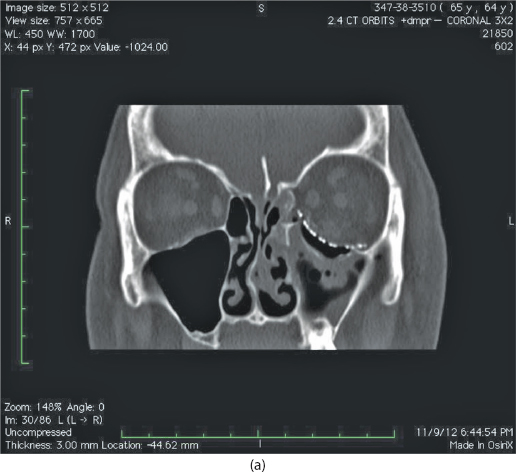

Isolated orbital floor fractures (blowouts) are often the result of impact injury to the globe resulting in a sudden increase in intraorbital hydraulic pressure. This kinetic energy is transmitted in an inferior and medial vector to the orbital floor (hydraulic theory) (Figure 13.1). Alternatively, the posterior transmission of a direct blow to the infraorbital rim causes buckling and resultant fracture of the orbital floor (buckling theory) (Figure 13.2). Fractures of the orbital floor can increase the volume of the orbit with resultant enophthalmos and hypoglobus. These can be highlighted on preoperative (Figure 13.3a–c) and postoperative (Figure 13.4a–c) computed tomographic (CT) scan imaging. In addition, the inferior rectus or periorbital soft tissue can become entrapped within the fracture line, resulting in restriction of extraocular eye movements. Table 13.1 indicates the special equipment used to surgically manage this injury.